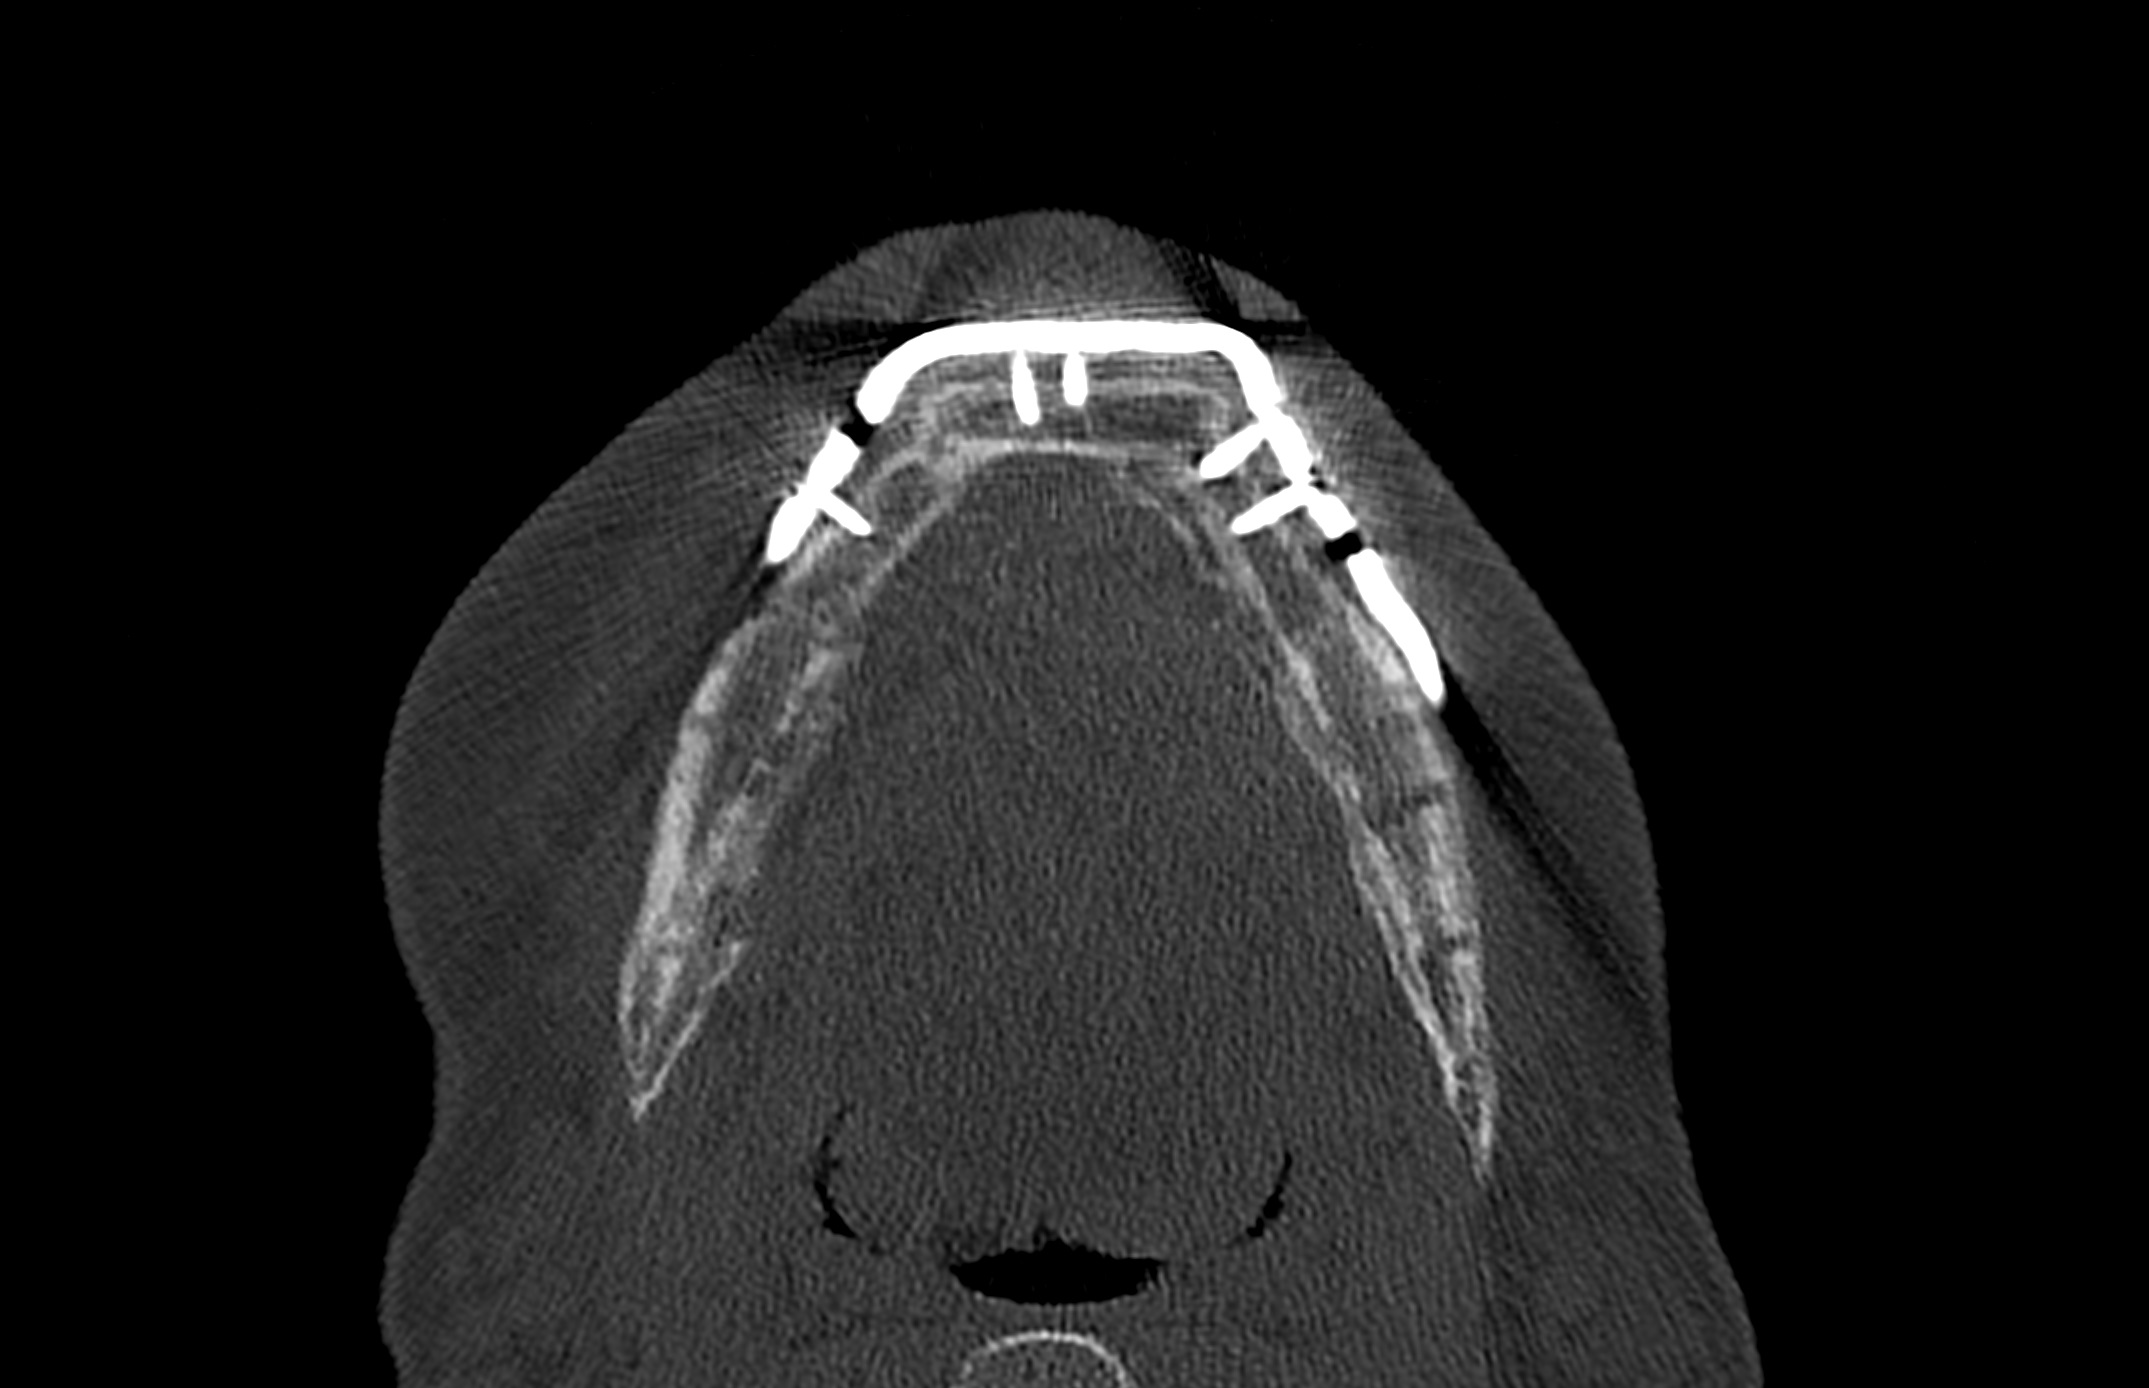

Scapular SLS templates or cutting guides were manufactured for secondary resection of the mandibular bone stumps, along with a set of STL models and a patient specific mandibular reconstruction plate (PSMP) (Fig. 5).

Postoperative imaging confirmed minimal intersegmental gaps to the mandibular remnants with undisturbed healing but limited overall bone volume (Fig. 7a-c). Therefore removal of the PSPMP and a preimplantological augmentation with corticocancellous iliac bone grafts followed 16 months later.

Finally, dental implants were inserted (Fig. 8).